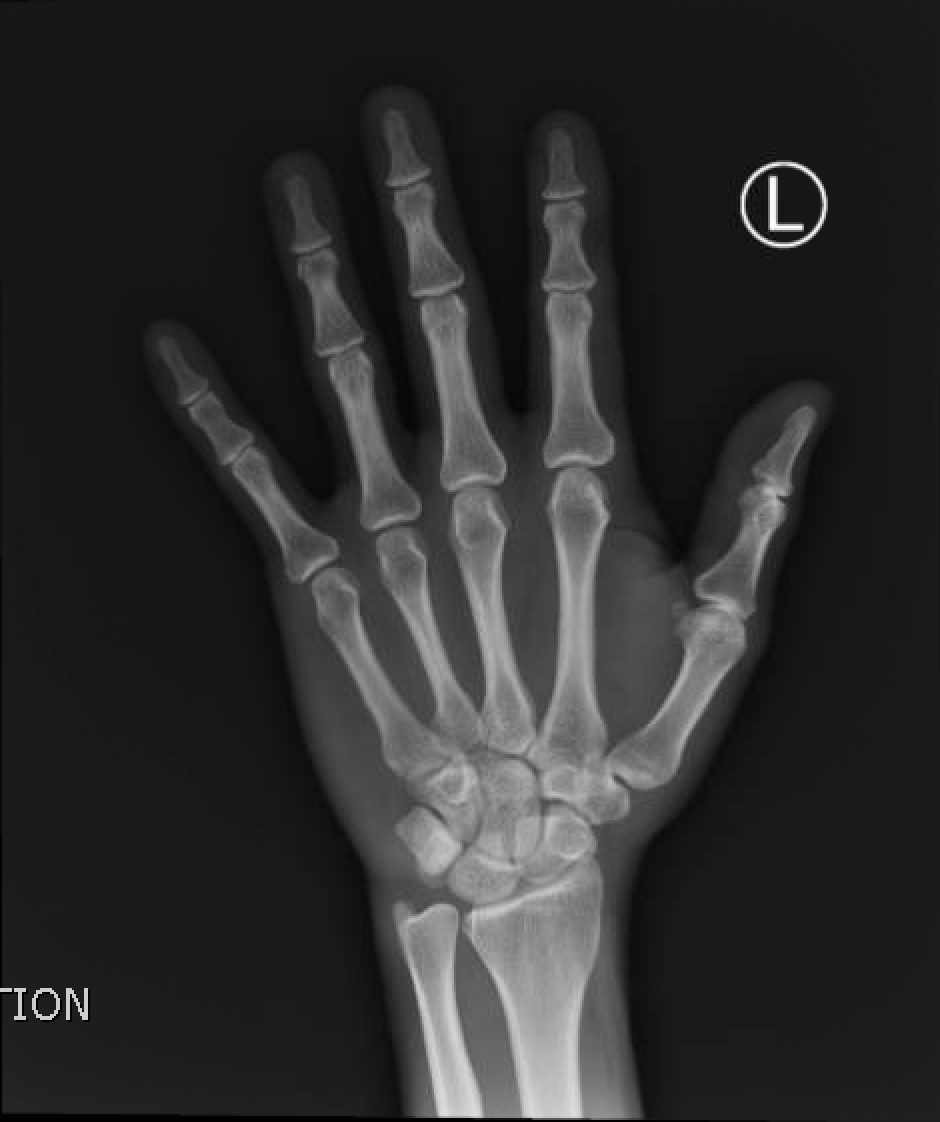

Physical exam revealed a 3cm laceration to the ulnar side of the dorsum of the left hand with minimal hand swelling. There was no exposed tendon or bone, the hand was neurovascularly intact and had full strength. A small barb was visualized and removed from the injury site. Radiograph of the left hand confirmed that there was no remaining barb (see normal x-ray).